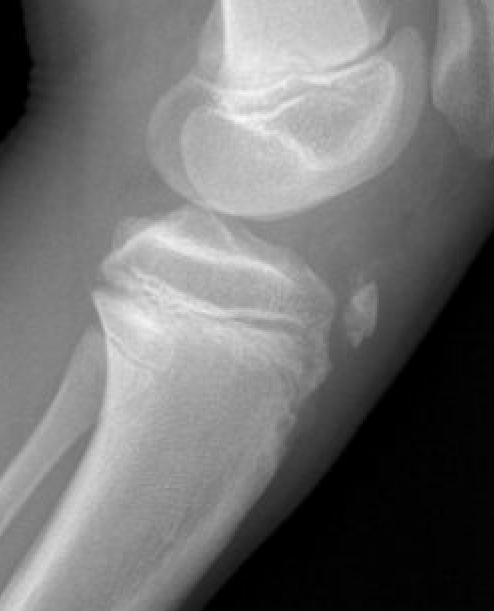

Type IB

Type IIB

Type III

Comminuted Type III